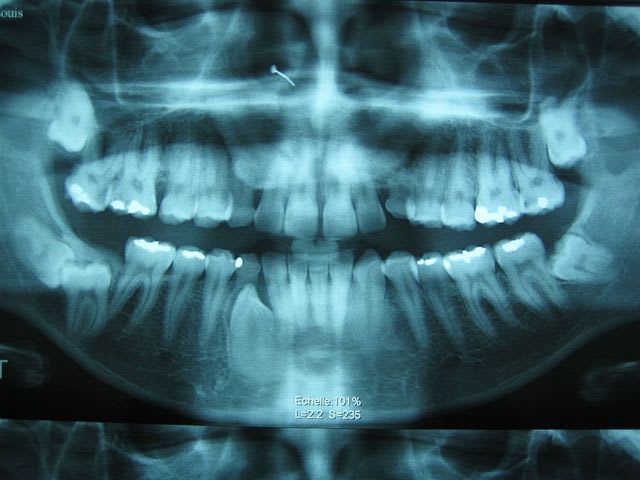

... j'ai profité de mes vacances _dernier jour aujourd'hui :((_ pour numériser ma collection d'OTP.

... premier cas: décharge de pistolet à grenaille dans le visage! (règlement de comptes entre toxicos)

... si vous savez compter ...

... dépassements de pâte ou de cônes d'argent ... même combat!

... racines zarbi!

... ganglion calcifié

... c'est grave Docteur?

... un oubli

Beau cas d'intégration osseuse!!

... comptez

... comptez ... les cônes d'argent!

... patiente née en 1946, endos datant d'une quarantaine d'années ... et pas de foyer ... la nature est bonne :)

Par contre pour sortir ces m*rdes, c'est la galère, ça casse très facilement.

... il a 27 ans.

... on fait ça à plusieurs: ortho, stomato, implanto peut-être.

Le gosse a l'air motivé.

la chevauchée fantastique!